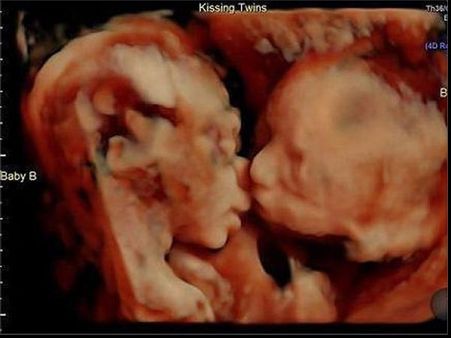

Ultrasound Photo Shows Twins Kissing!

It was a regular scan for this couple until they saw the images of the ultrasound scan clearly. It showed their twins kissing and the couple cannot wait for their arrival!

The Couple Were Confused With The Images

The couple were worried and confused when they saw the images, as these did not look normal.

It Took A Few Seconds For Them To Understand…

The couple got a clearer picture of the twins and that is when they discovered that the twins were actually kissing each other! How adorable is that!